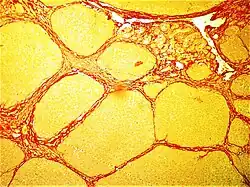

- Lipedema (fat cells, typically in lower limbs)